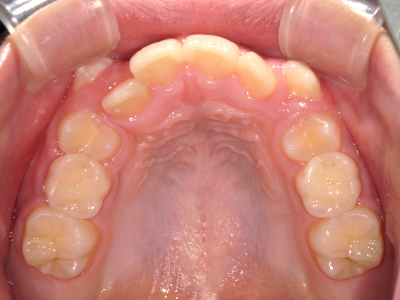

歯並びの相談に来られるお子様は、口呼吸をしているケースが多く、これが歯並びに大きな影響を与えています。

↓ - 上あごが狭くなる

↓ - さまざまな不正咬合が生じる

ないき歯科クリニックでは、上あごの成長不足を補い、鼻呼吸を獲得しつつ歯列を整え、将来のお口をより健康な状態にすることをゴールに定める矯正治療をおこなっています。